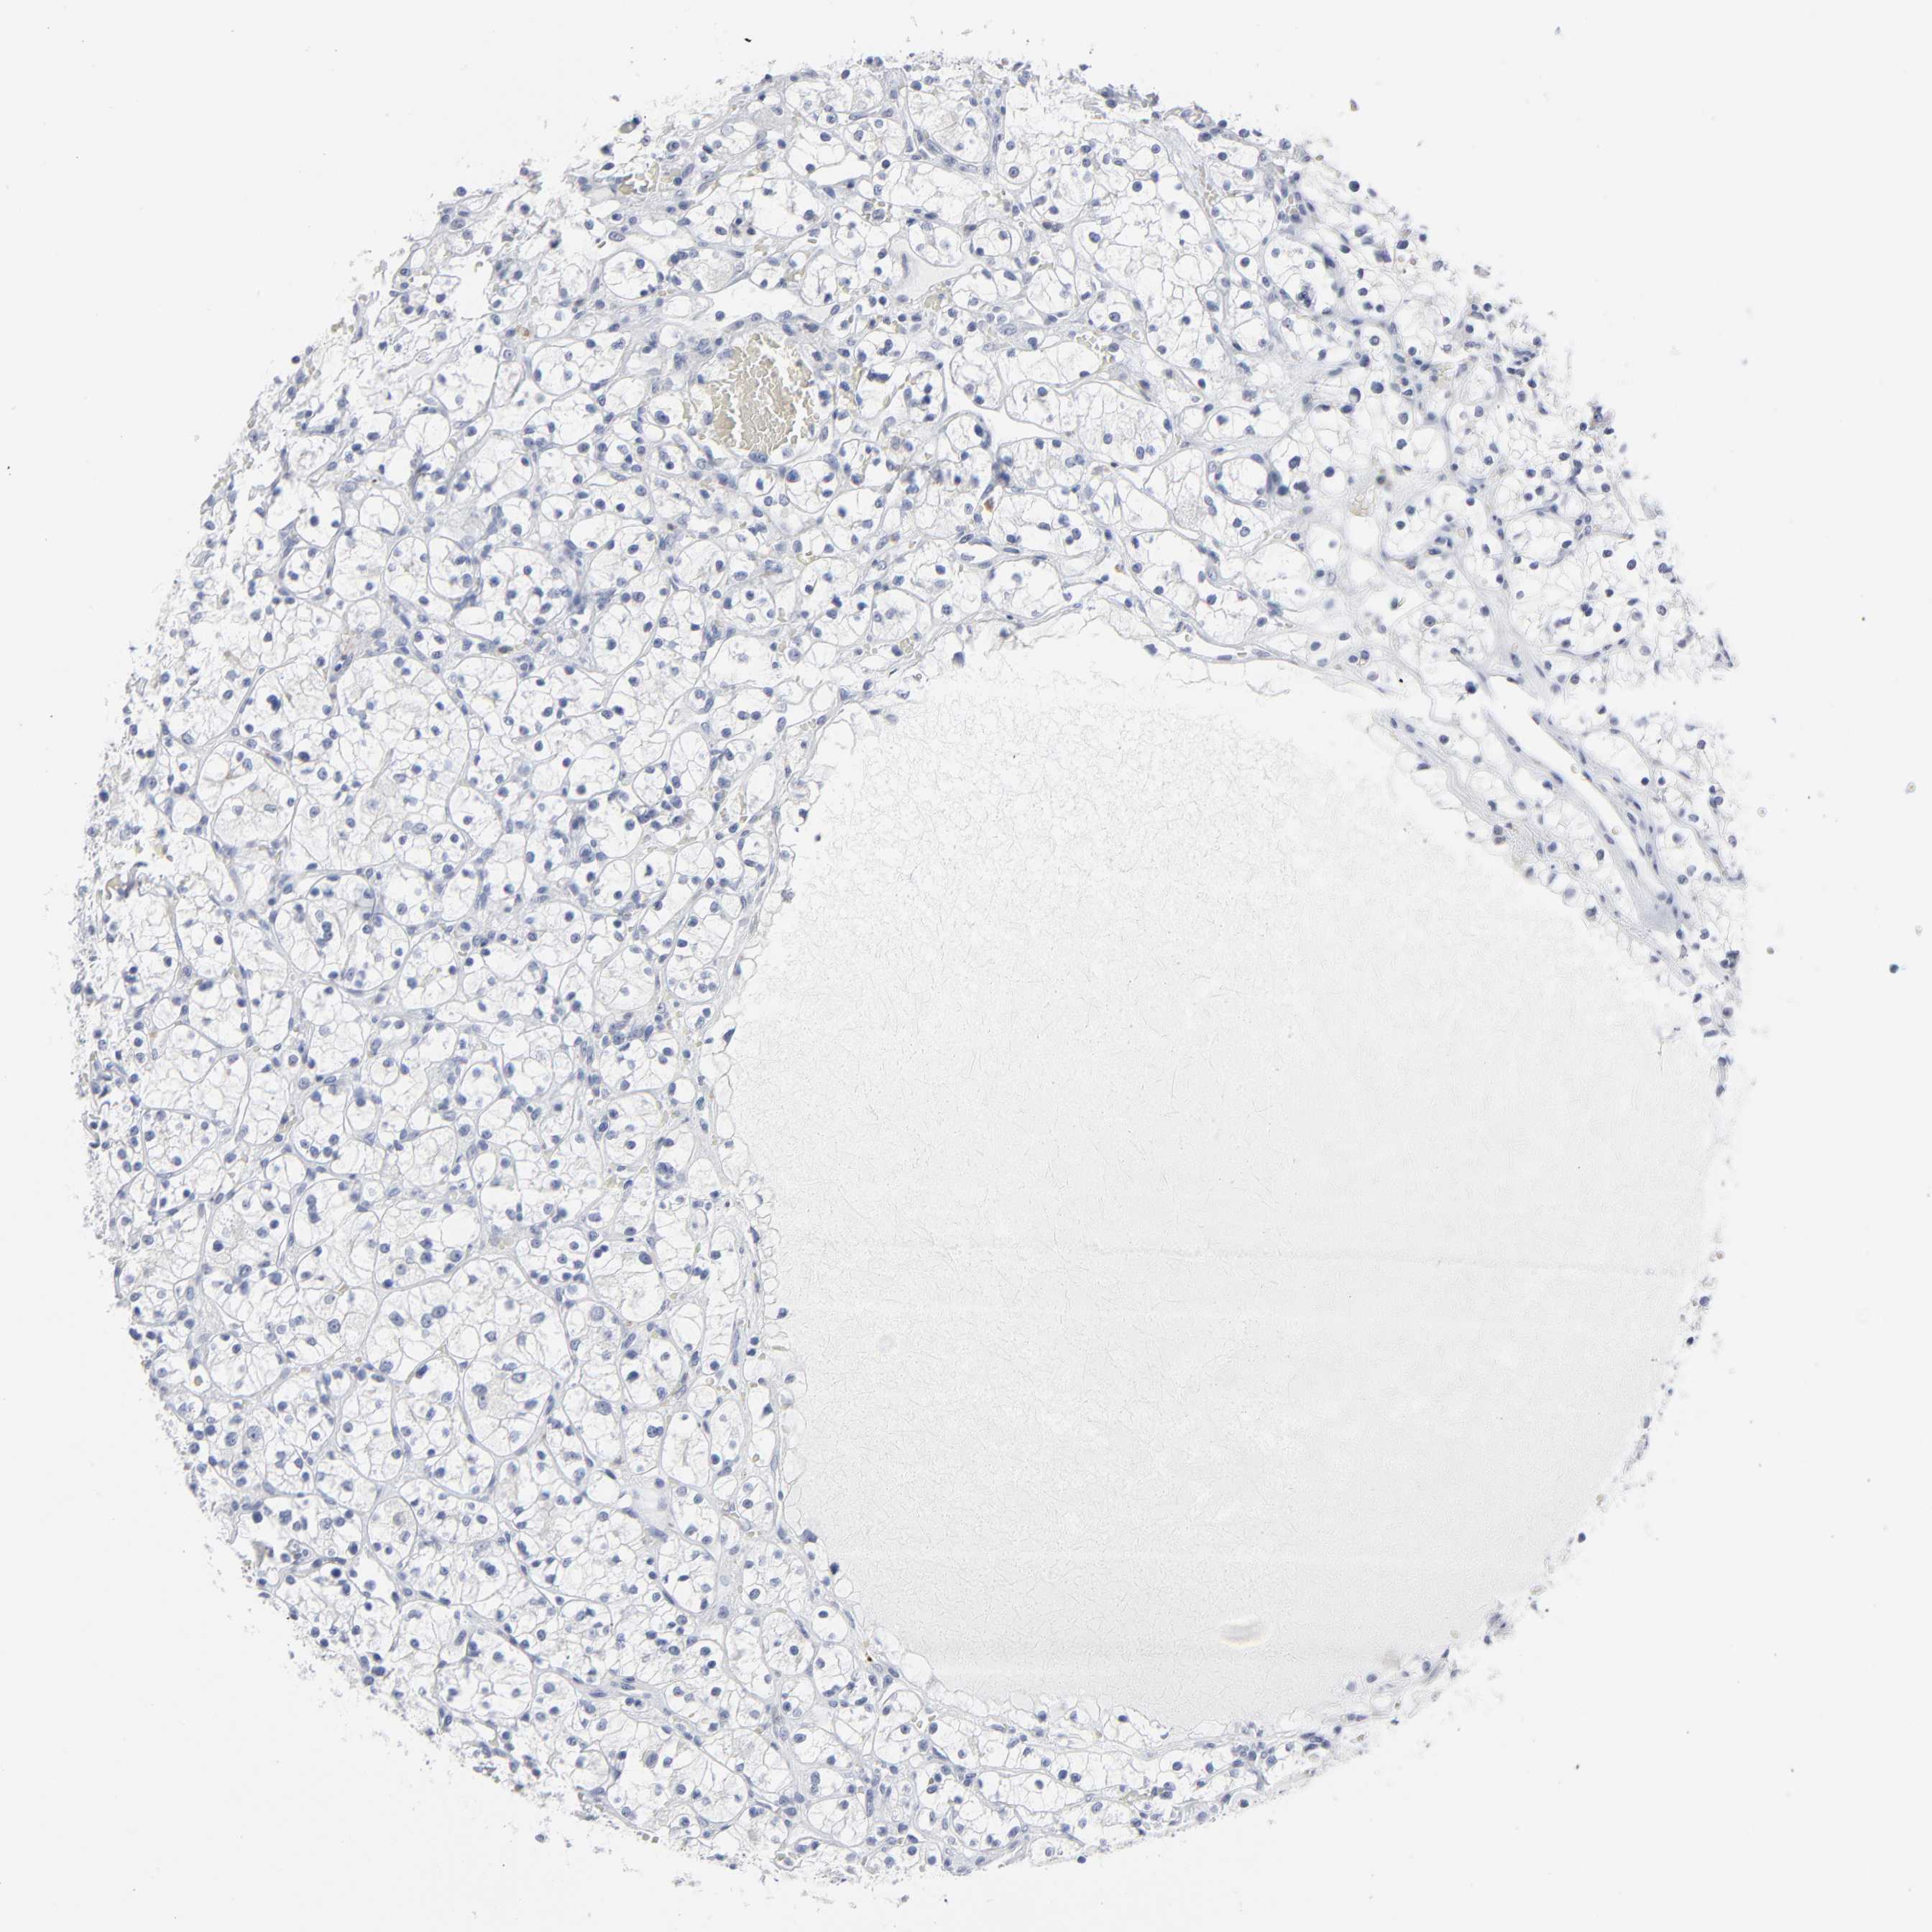

KIDNEY RENAL CLEAR CELL CARCINOMA (VALIDATION) - Interactive survival scatter ploti

The Survival Scatter plot shows the clinical status (i.e. dead or alive) for all individuals in the patient cohort, based on the same data that underlies the corresponding Kaplan-Meier plots. Patients that are alive at last time for follow-up are shown in blue and patients who have died during the study are shown in red.

The x-axis shows the expression levels (FPKM) of the investigated gene in the tumor tissue at the time of diagnosis. The y-axis shows the follow-up time after diagnosis (years). Both axes are complimented with kernel density curves demonstrating the data density over the axes. The top density plot shows the expression levels (FPKM) distribution among dead (red) and alive patients (blue). The right density plot shows the data density of the survived years of dead patients with high and low expression levels respectively, stratified using the cutoff indicated by the vertical dashed line through the Survival Scatter plot. This cutoff is automatically defined based on the FPKM cutoff that minimizes the p-score. The cutoff can be changed by dragging the vertical line or by entering a cutoff value in the square labeled "Current cut-off".

Under the Survival Scatter plot the p-score landscape (black curve; left axis) is shown together with dead median separation (red curve; right axis). Dead median separation is the difference in median mRNA expression between patients who have died with high and low expression, respectively. It is calculated as follows: median FPKM expression of dead patients with high expression - median FPKM expression of dead patients with low expression. This is intended to aid the user in visually exploring custom cutoffs and the associated p-scores and dead median separation.

Individual patient data is displayed and can be filtered by clicking on one or more of the category buttons on the top of the page. Categories describing expression level and patient information include: high, low, alive, dead, female, male and tumor stages. The scale of the x-axis can be toggled between linear and log-scale by clicking on the "x log" button. Mouse-over function shows TCGA ID, patient information and mRNA expression (FPKM) for each patient.

& Survival analysisi

Kaplan-Meier plots summarize results from analysis of correlation between mRNA expression level and patient survival. Patients were divided based on level of expression into one of the two groups "low" (under cut off) or "high" (over cut off). X-axis shows time for survival (years) and y-axis shows the probability of survival, where 1.0 corresponds to 100 percent.

Survival analysis data not available.

TCGA RNA samplesi

RNA-seq data is reported as average FPKM (number Fragments Per Kilobase of exon per Million reads), generated by the The Cancer Genome Atlas (TCGA) .

Normal distribution across the dataset is visualized with box plots, shown as median and 25th and 75th percentiles. Points are displayed as outliers if they are above or below 1.5 times the interquartile range. FPKM values of the individual samples are presented next to the box plot.

Average pTPM 0.0

Number of samples 100